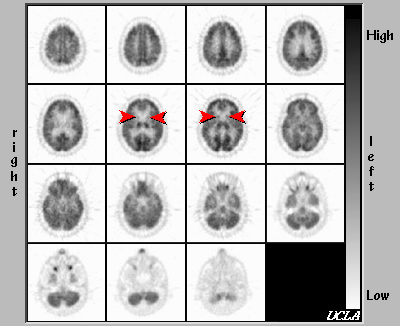

- Findings Consistent with Huntington's Disease

There is marked hypometabolism in the heads of caudate and putamen bilaterally (arrowheads), consistent with Huntington's disease. Metabolism is normal in the cerebral cortex and cerebellum.